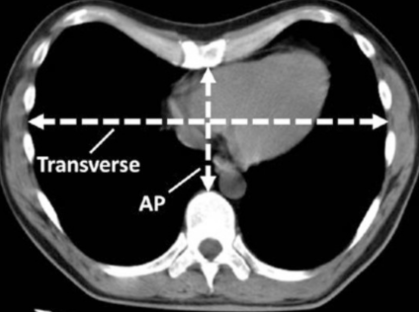

Múltiples estudios han tratado de vincular la disfunción pulmonar con la severidad del PEX, valorado a través de diferentes índices de severidad siendo el más utilizado el índice de Haller (IH). Éste índice es tomográfico y se calcula como la relación entre la mayor distancia transversal del tórax y la mínima distancia anteroposterior del tórax (midiendo del borde posterior del esternón a la cara anterior vertebral), a la altura del sitio de mayor hundimiento (Figura 2)21.